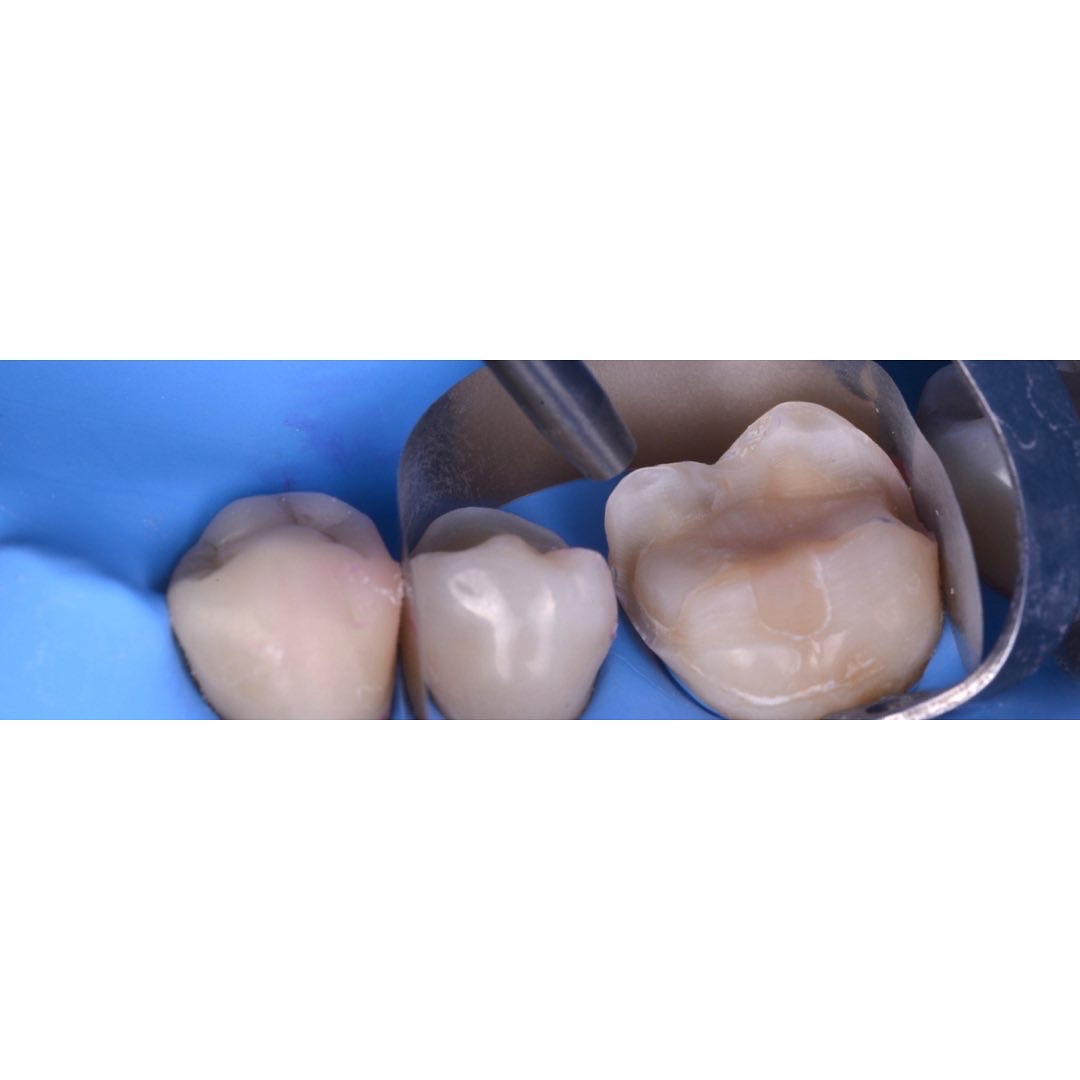

| 治療内容 | 5前歯をジルコニアベースのセラミッククラウンに置き換えました。 |